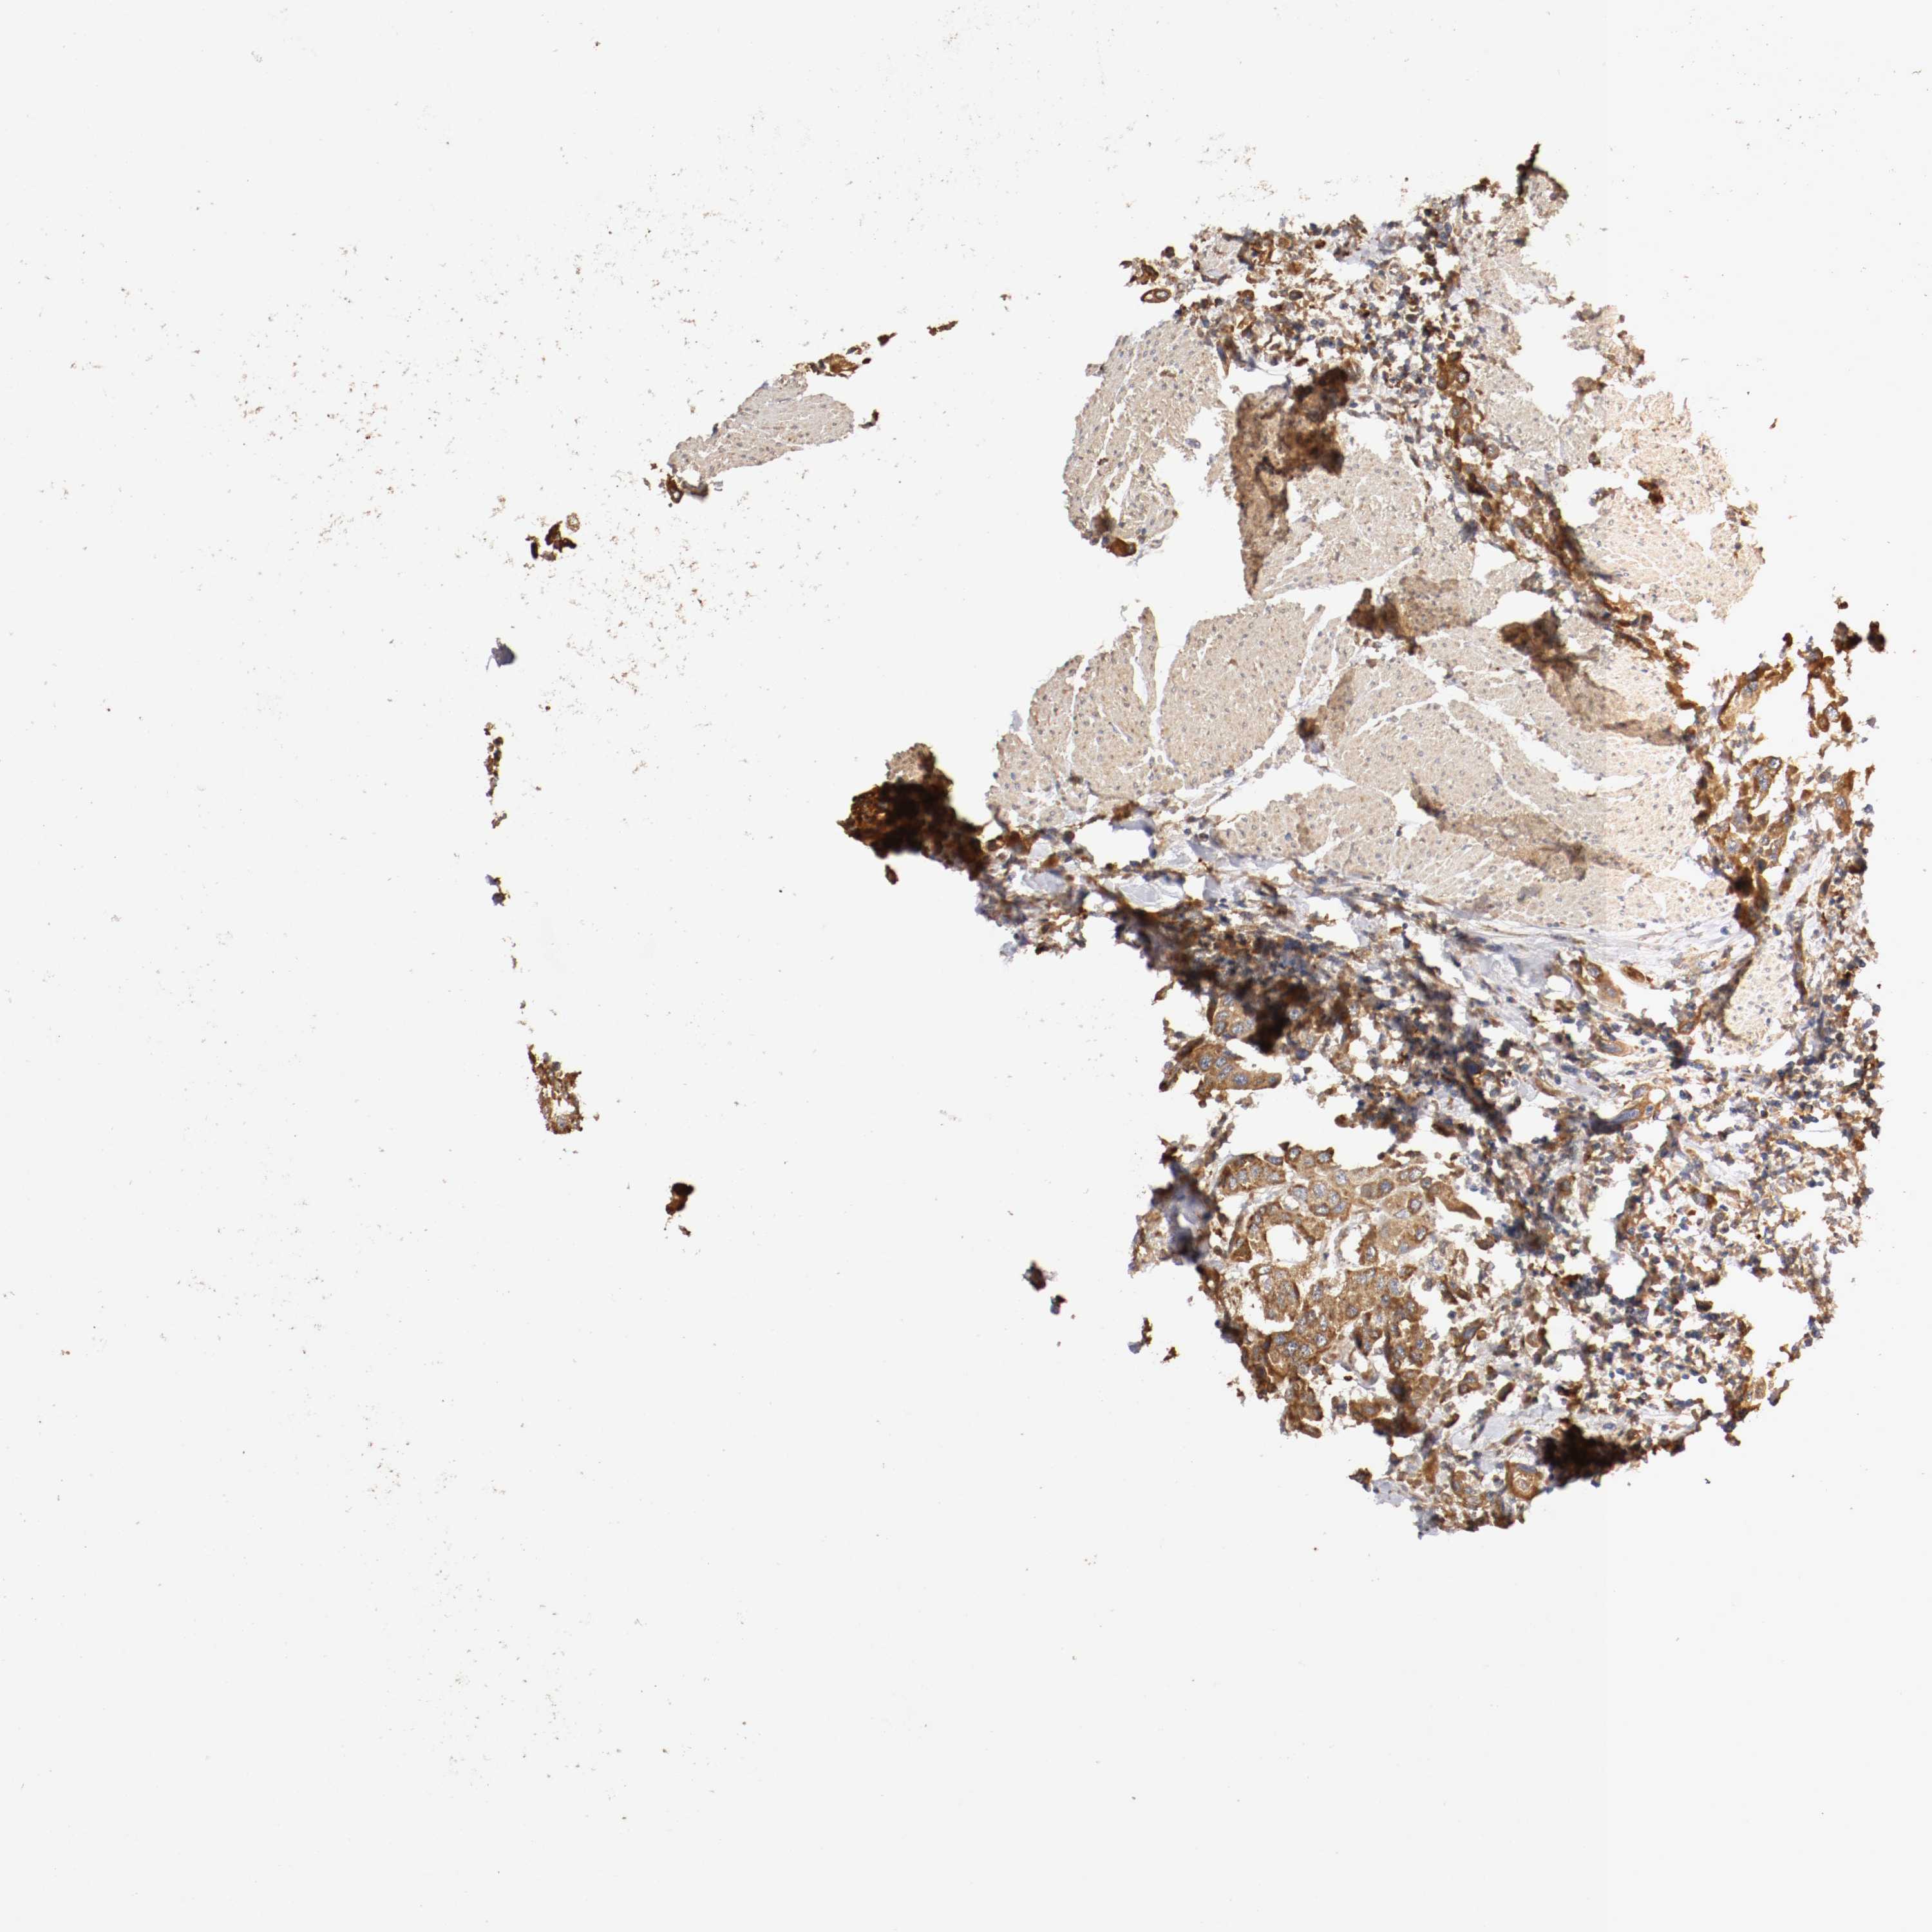

UROTHELIAL CANCER - Protein expressioni

A mouse-over function shows sample information and annotation data. Click on an image to view it in a full screen mode. Samples can be filtered based on level of antibody staining by selecting one or several of the following categories: high, medium, low and not detected. The assay and annotation is described here.

Note that samples used for immunohistochemistry by the Human Protein Atlas do not correspond to samples in the TCGA dataset.

Antibody stainingi

Antibody staining in the annotated cell types in the current human tissue is reported as not detected, low, medium, or high, based on conventional immunohistochemistry profiling in selected tissues. This score is based on the combination of the staining intensity and fraction of stained cells.

Each image is clickable and will lead to virtual microscopy that enables deeper exploration of all samples and also displays staining intensity scores, fraction scores and subcellular localization as well as patient and tissue information for each sample.

Antibody HPA004811

Antibody HPA017066

Urothelial carcinoma, High grade

Urothelial carcinoma, Low grade